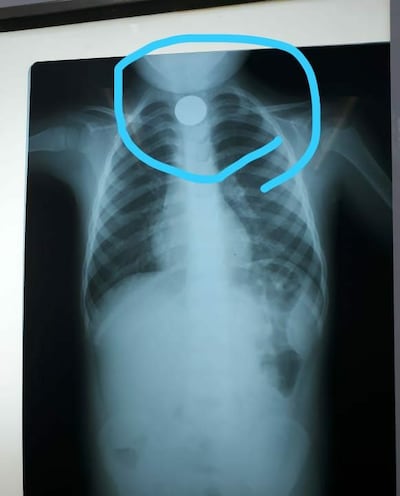

Por el tamaño de la moneda, se quedó atascada en el tercio superior del esófago y la extracción solo podía ser hecha mediante un procedimiento quirúrgico bajo sedación, informó la doctora María José Guillén. Estaba internado en un centro distrital de Santaní.

Por su parte, la Dra. Guillén dijo que el niño llegó deshidratado, entonces lo ingresaron, lo hidrataron y se lo estabilizó para que dejara de vomitar. Quedó en reposo enteral, y recién alrededor de las 15:00 se le sometió a cirugía. Sucede que el único quirófano de pediatría estaba operando a niños con riesgo de vida, que son pacientes de emergencia.